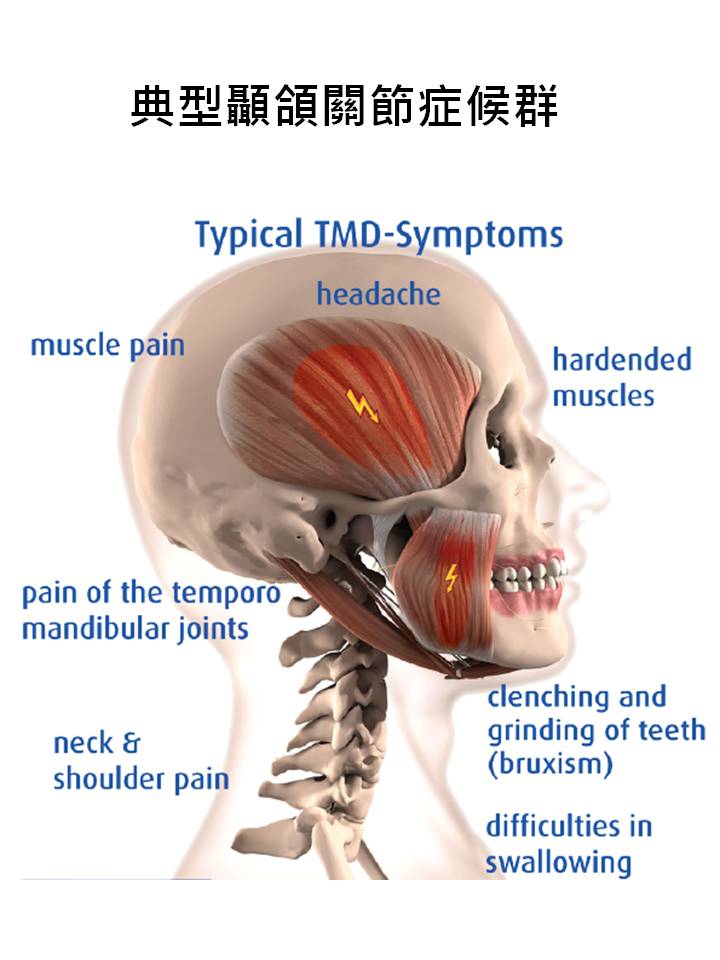

換句話說,在水平衡咬合板上咬下去會導致使咬合力均勻分佈在整個咬合處的液體,減少了TMJ承受壓力和痛苦並確保緩解並使身體自然平衡,從而減輕TMJ疼痛并改進的功能。

換句話說,在水平衡咬合板上咬下去會導致使咬合力均勻分佈在整個咬合處的液體,減少了TMJ承受壓力和痛苦並確保緩解並使身體自然平衡,從而減輕TMJ疼痛并改進的功能。

TMJ承受壓力和痛苦並確保緩解並使身體自然平衡,從而減輕TMJ疼痛并改進的功能。

TMJ承受壓力和痛苦並確保緩解並使身體自然平衡,從而減輕TMJ疼痛并改進的功能。